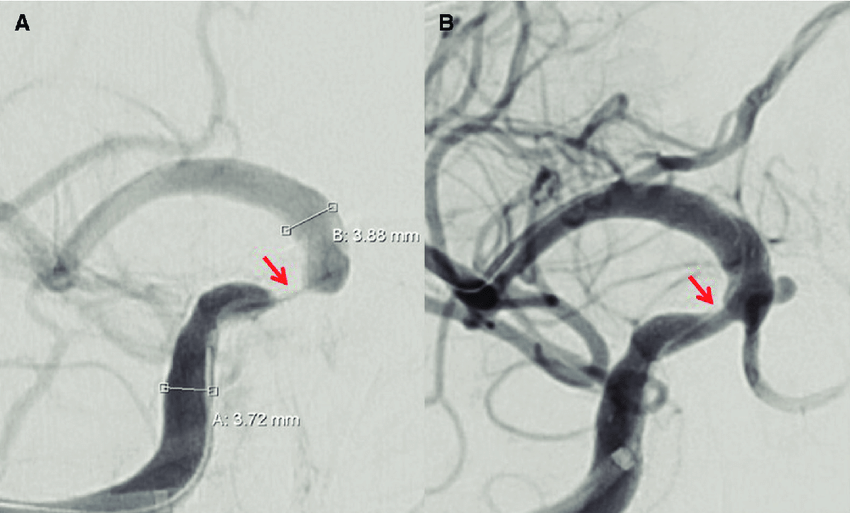

ACV isquémico agudo: tratamiento endovascular con o sin trombolisis

26 enero 2021